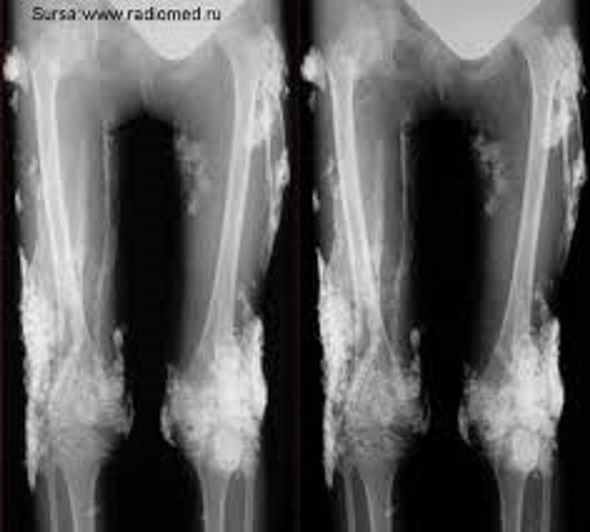

Calcificarea articulației și tendoanelor Radiologii găsesc frecvent calcificarea în articulații și tendoane. Calcificarea articulației și a tendoanelor sunt relativ frecvente. De exemplu, aproximativ 3- 15% dintre oameni au calcificarea unui tendon, numit tendinită calcifică. Persoanele cu tendinită calcifică pot simți uneori o „înțepătură” a tendonului calcificat. Cu toate acestea, afecțiunea poate provoca, de asemenea, durere semnificativă sau deloc simptome. Cercetările sugerează că aproximativ 45% dintre persoanele în vârstă de 85 de ani și peste au depozite de calciu în cartilajul articulațiilor lor.

Persoanele cu o calcificare a tendoanelor nedureroase sau de tendon nu necesită tratament. Cu toate acestea, pot necesita tratament dacă încep să apară dureri. Niciun tratament nu poate îndepărta depunerile de calciu din cartilajul articulațiilor, astfel încât medicii tind să se bazeze pe injecții de glucocorticoizi, colchicină orală și AINS, care pot ajuta la ameliorarea durerii și a inflamației subiacente. Chirurgia poate fi necesară pentru unele persoane cu această afecțiune.